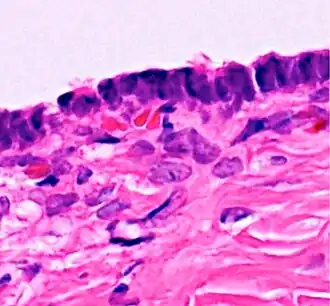

| Micrograph of serous carcinoma, a type of serous tumour. |

A serous tumour is a neoplasm that typically has papillary to solid formations of tumor cells with crowded nuclei, and which typically arises on the modified Müllerian-derived serous membranes that surround the ovaries in females. Such ovarian tumors are part of the surface epithelial-stromal tumour group of ovarian tumors. They are common neoplasms with a strong tendency to occur bilaterally, and they account for approximately a quarter of all ovarian tumors.